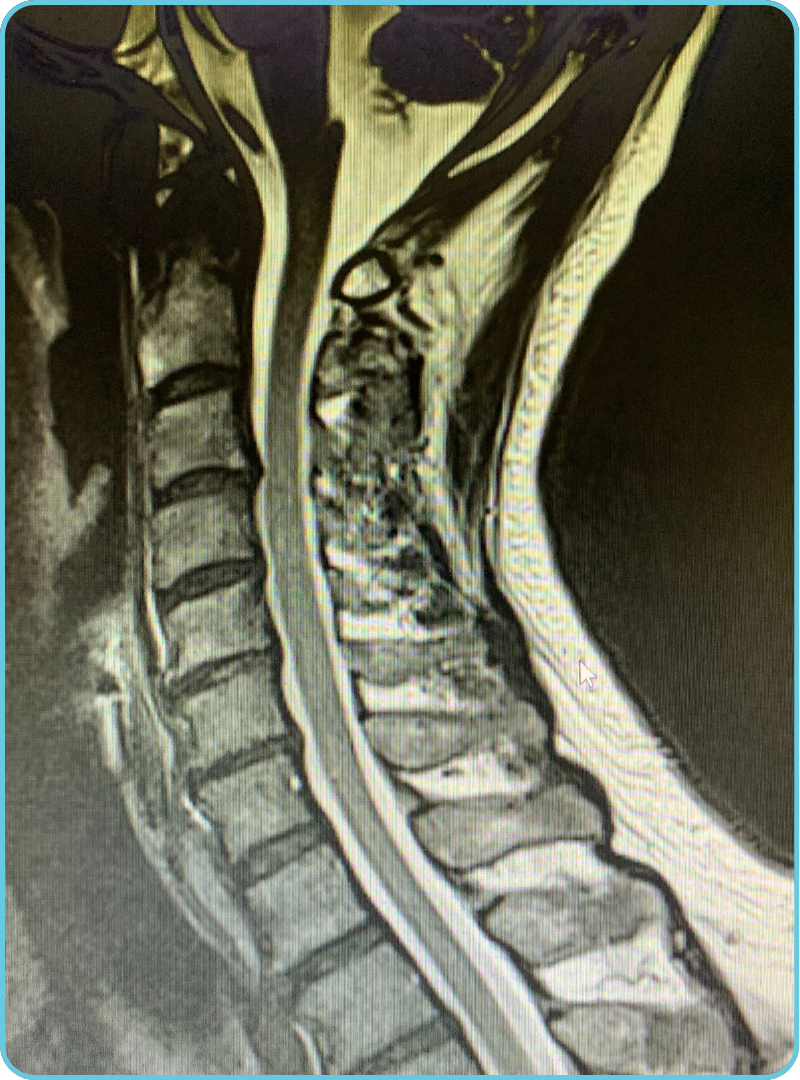

At CSDC, Dr. Chong focuses on comprehensive spine consultations and providing tailored treatment plans, leading to effective results for people suffering from chronic back pain and neck pain, degenerative, bulging, and herniated discs often with severe low back pain, sciatic pain, or pinched nerves. He utilizes his many years of practice, to carefully assess and analyze patient X-rays, MRI’s, and related clinic results via NETCARE, assisting him to provide patients with an accurate working diagnosis during each spine consultation.

We offer both Cervical and Lumbar spine decompression.